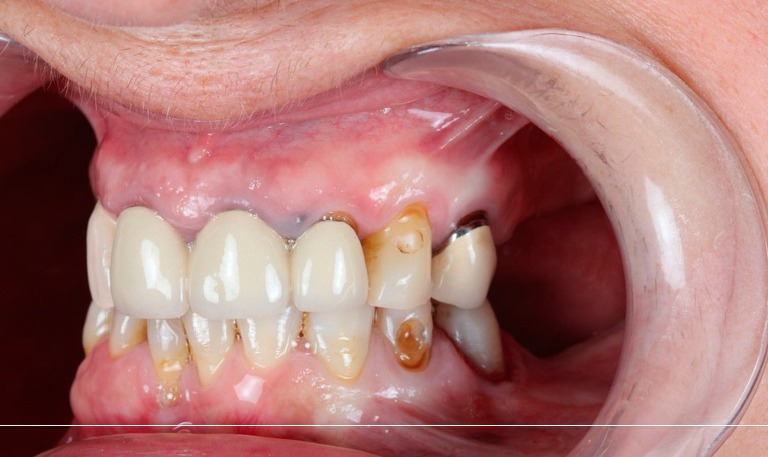

Odontología Estética. Coronas

BeforeAfter